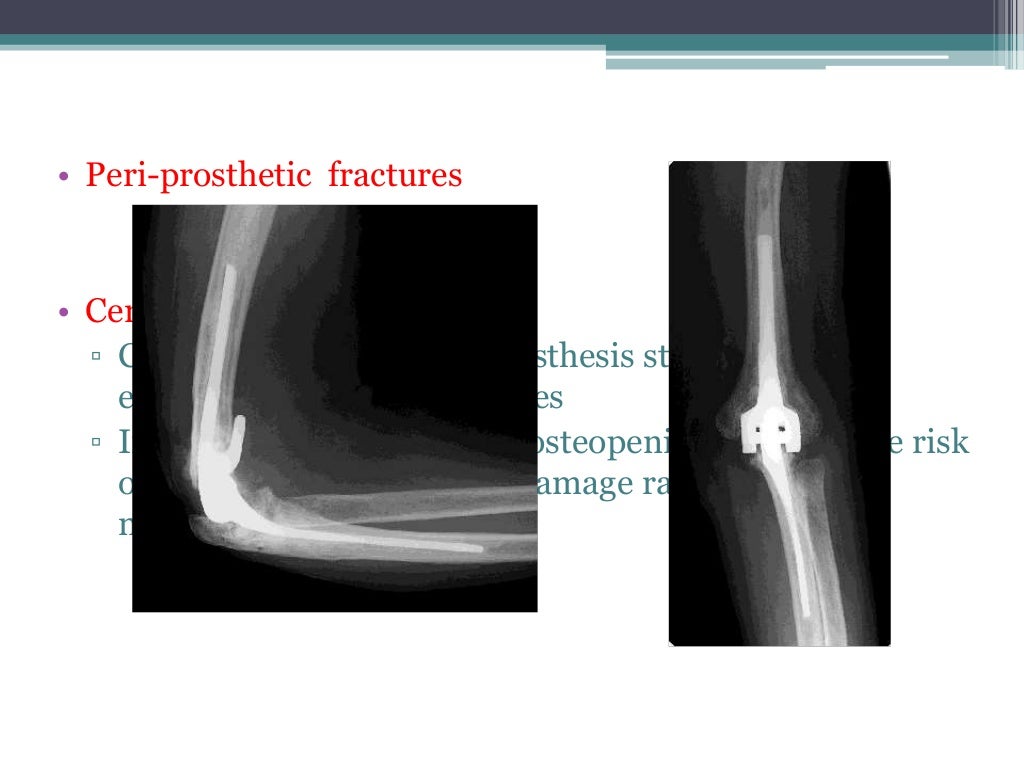

Total elbow arthroplasty